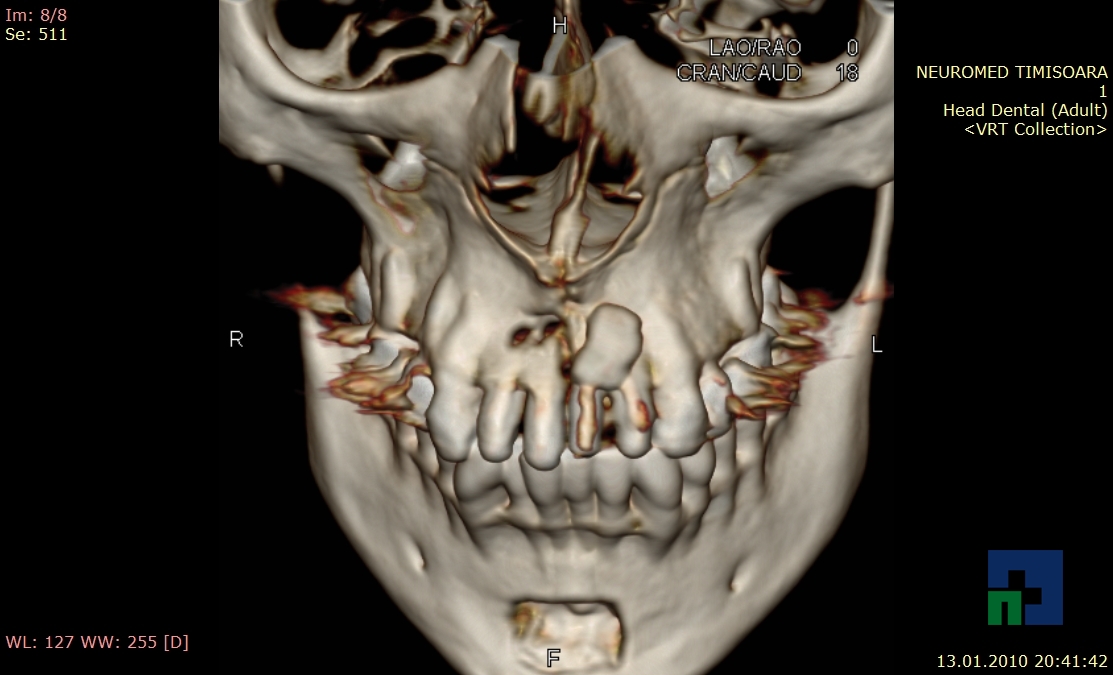

- Diagnosticul fracturilor:

-

- Unice

- Multiple

- Cu înfundare

- Complexe cranio-sinusale

- Complexe cranio-etmoidale

- Complexe cranio-orbitare

- Complexe cranio-faciale